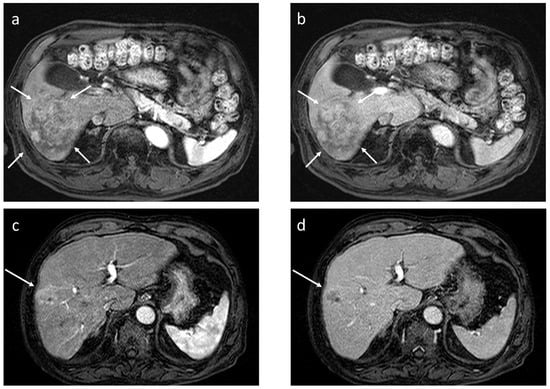

In a sub-analysis of our previous study [24], we investigated which pathological factors are significantly related to ECVHCC, and multivariable analysis revealed that positive inflammatory cell infiltration, negative fibrous capsule, and positive scirrhous component are the independently significant factors as determinants of ECVHCC (unpublished data). Independently, Maehara et al. [48] reported that higher amounts of intratumoral collagen and elastin were significantly associated with certain macroscopic types (confluent multinodular type rather than simple nodular type), positive intratumoral fat, and immunohistochemical subtypes (biliary-stem cell type, rather than Wint-βcatenin or both negative types) [51,52,53,54,55], in addition to positive inflammatory cell infiltration, negative fibrous capsule, and positive scirrhous component—factors completely overlapping with those related to ECVHCC in our sub-analysis. Although our pathologists do not routinely perform immunohistochemical staining for HCC, and therefore we do not have direct evidence that ECVHCC is related to immunohistochemical subtypes, the similarity in features, as seen on routine hematoxylin and eosin staining suggests that ECVHCC may indeed correlate with immunohistochemical subtypes of HCC. Because immunohistochemical subtypes have been reported to be closely related to gene signatures, immunological tumor microenvironment, and clinicopathological features of HCC (Figure 7) [51,52,53,54,55], these observations may suggest the possibility that ECVHCC can be used in the future as an indicator of biological aggressiveness of HCC, or as a predictor of response to systemic therapy such as immune checkpoint inhibitor or anti-VEGF agents.

Recently, Wang et al. [56] reported that the ECV of HCC may be used to predict Ki-67 positivity of HCC. Ki-67 expression usually indicates high proliferative status of malignant tumors, and as a result, biological aggressiveness of the neoplasm. Their observation that higher ECV may suggest a higher likelihood of Ki-67 expression is quite in accordance with our above-mentioned speculation. Li et al. [57] also reported machine learning models including the ECV of HCC can predict its histological grades (high vs. low grade). Thus, evidence has been accumulated suggesting that ECV, an important determinant of washout status at the EqP, is closely related to histological grades or the biological aggressiveness of HCC. Regarding Ki-67, however, Deng et al. [58] has reported the opposite result; namely, Ki-67 expression was inversely related to the ECV of HCC. Further investigation would be needed to solve this contradiction. Further, Fu et al. [59] reported that higher ECV of HCC is related to longer progression-free survival and overall survival in patients receiving immune checkpoint inhibitors. This is in accordance with previous observation, because higher ECV is associated with the biliary/stem cell immune histochemical subclass [51,52,53,54,55], which is immune hot compared to the other two subclasses (Figure 7) [51,52,53,54,55]. The correlation between the ECV of HCC and patient survival after chemoembolization has also been reported [60], but with equivocal results.

Figure 7. Details of the relationship between immunohistochemical (IHC) subtypes of hepatocellular carcinoma vs. gene signatures, vs. tumor microenvironments (TMEs), and vs. clinicopathological features. It has been shown that the amount of collagen and elastin within hepatocellular carcinoma is large in B/S type, and less in −/−, or W/B types [48]. B/S, biliary/stem cell; W/B, Wint/β-catenin; −/−, both B/S and W/B negative; LGR5, Leucine-rich repeat-containing G-protein coupled receptor 5; OATP1B3, organic anion transporting polypeptide 1 B 3; EOB, ethoxybenzyl diethlenetriamine pentaacetic acid; poly7, polysomy of chromosome 7; CTNNB1, βcatenin gene; KRT19, keratin 19; EpCAM, epithelial cell adhesion molecule; TGF-β, transforming growth factor-β; Sci, scirrhous; SH, steatohepatitis; AFP, alpha-fetoprotein; VP, portal venous invasion; +++, severe; +, mild. Reproduced from reference [53] with permission.